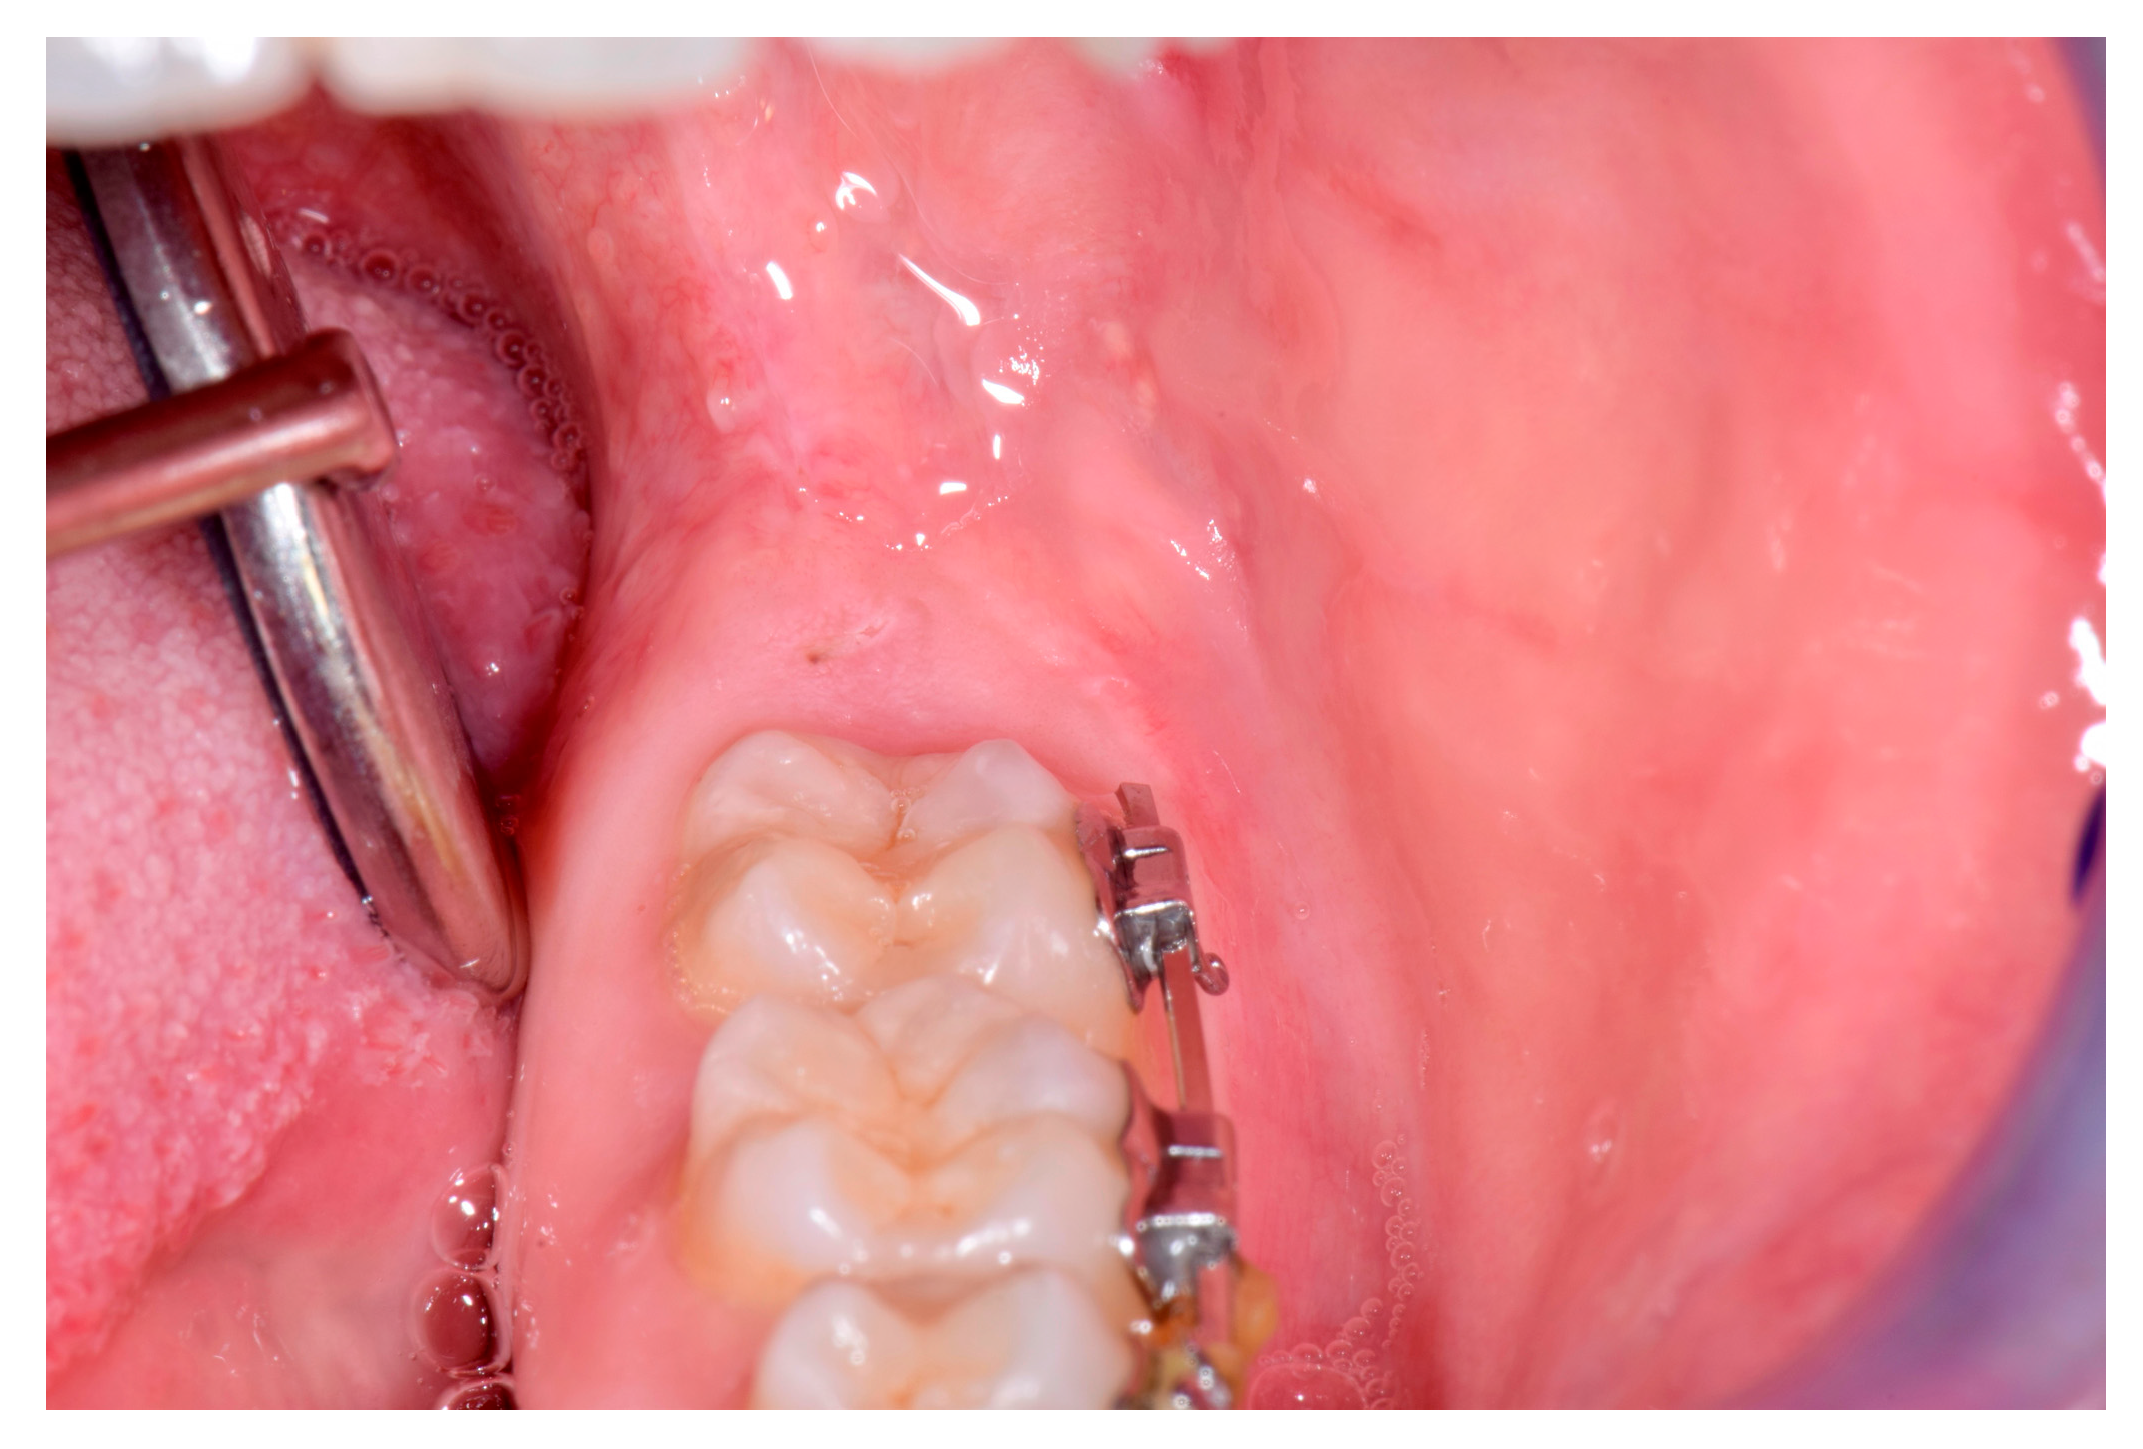

Nevus in the Oral Cavity †

2. Case

3. Treatment